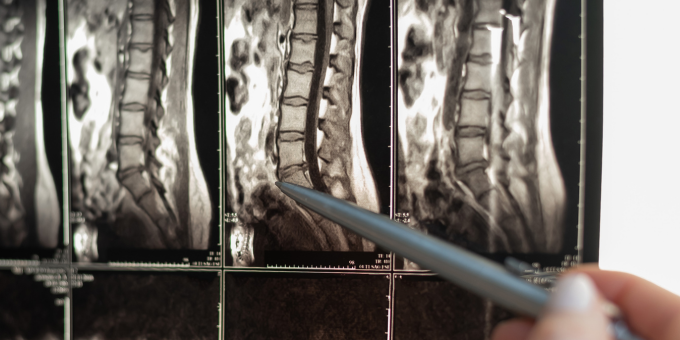

Degenerative disc disease (DDD) is a condition characterised by the breakdown of the intervertebral discs, which are the soft, gel-like cushions located between the vertebrae of the spine. These discs play a crucial role in providing support, flexibility, and shock absorption to the spine, allowing for smooth movement and preventing the vertebrae from rubbing against each other.

The intervertebral discs consist of a tough outer layer called the annulus fibrosus and a soft, gel-like centre called the nucleus pulposus. With age and wear and tear, these discs can degenerate, leading to changes in their structure and function. Several factors contribute to the development of DDD, including: